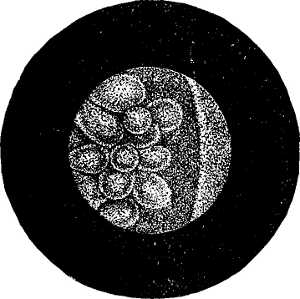

| XII. SURGERY.—Papillomatous Tumor of the Bladder, demonstrated by Means of Lister's Electro-cystoscope.—By F. N. Otis, M.D.—An interesting instance of the use of an exploratory electric light.—2 illustrations. | 10354 |

| Tumors of the Bladder Diagnosed by Means of the Electro-Endoscopic Cystoscope.—By Dr. Max Nitze.—The same general subject in further detail, giving the German practice.—5 illustrations. | 10353 |